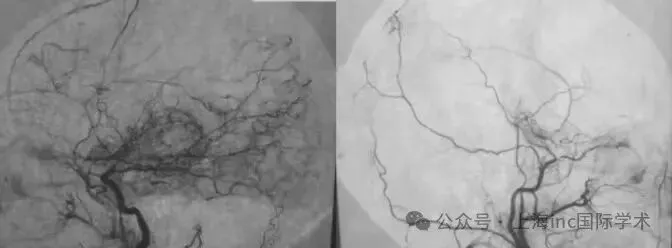

脑血管造影显示,小雅属于右侧单侧烟雾病,Suzuki分期为II期(或II-III期过渡期)。令人惊讶的是,其脑血流(CBF)检查并未显示明显下降。这意味着小雅的脑血管已开始出现"堵塞",身体正努力通...